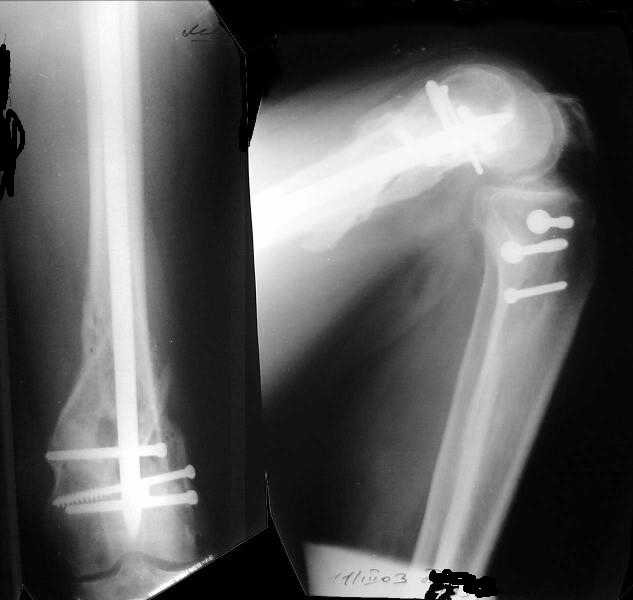

Отправитель: V. M. Iyer 01 Январь 2004, 15:17

1

2

The mobilisation of knee is started immediately from the second day. Weight bearing is permitted as in any other interlocked nailing. That is, Toe touch to start with and within four days, partial to in another two weeks, full weight bearing. Of course that is assuming that the correct size nail has been used. Up to 70 kg body weight, 11no will be good enough and 12mm if more.Usually at the 1st followup, at 6 weeks time, they have full flexion..I

have seen a few surgeons putting in a drain, but I have not found it unnecessary. There has never been any effusion needing active treatment.

Enclosing a recent intraop picture

V M Iyer